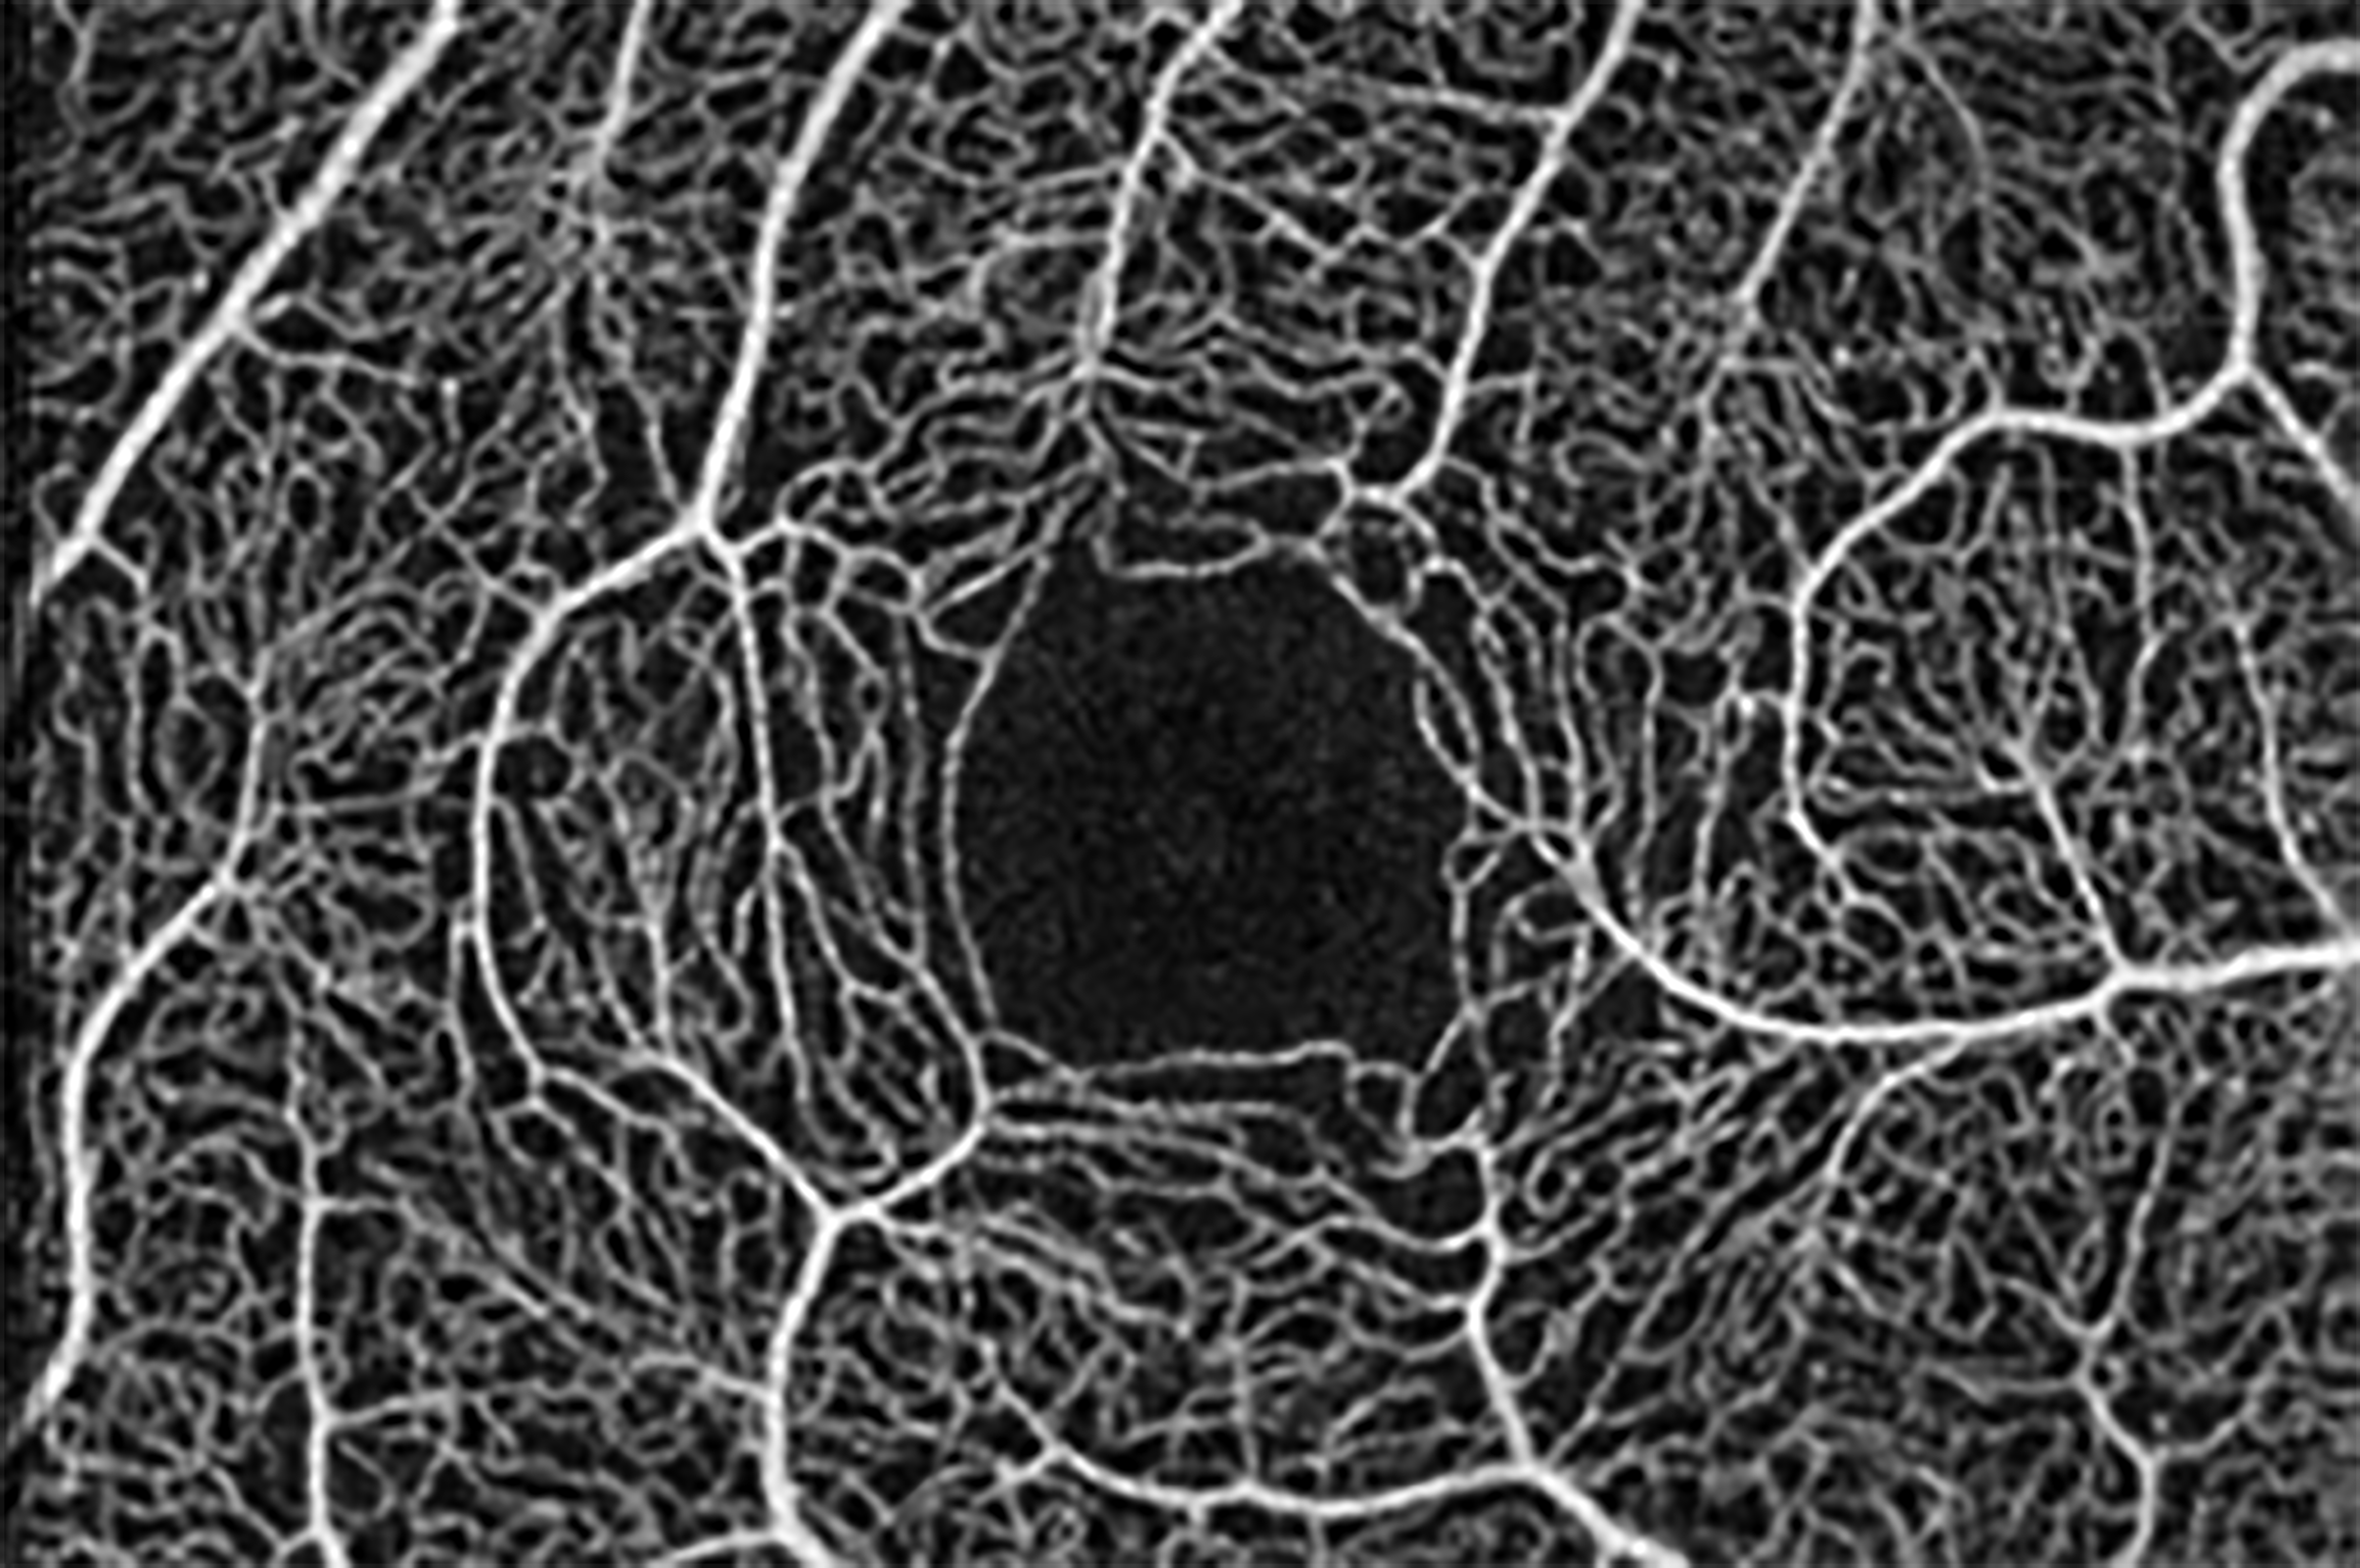

OCT-A Image

OCT-A image, centered on the fovea, of a subject without ocular or systemic pathology.

OCT-A image centered on the fovea, of a subject with macular-foveal capillaries also known as a “fragmented” foveal avascular zone.